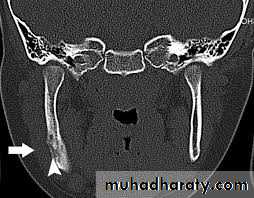

Radiographical appearance ;

It is possible to see a patient with acute osteomyelitis that has a normal-appearing orthopantomogram. However, one can often see the appearance of "moth-eaten" bone or sequestrum of bone, which is the classic appearance of osteomyelitis.14

Computerized tomography (CT) scans have become the standard in evaluating maxillofacial pathology such as osteomyelitis. its sensitive in late stage when 30%-50% of the bone demineralized.